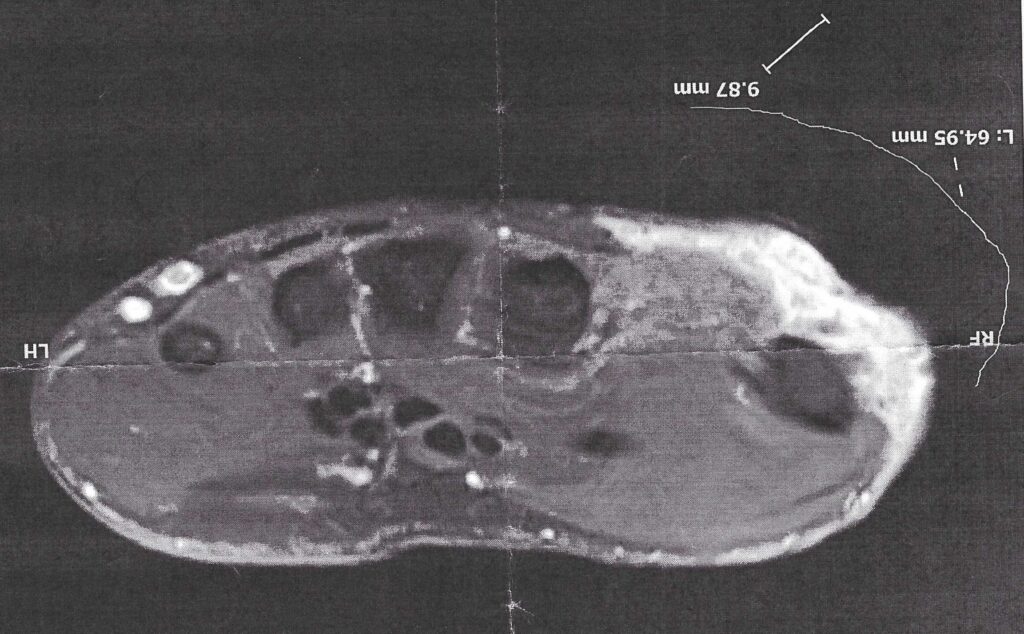

So deep in fact that it is right up against my bone. The image on the right is a single image of my MRI. The darker almost circle spots are my bones. You can see my pinky on the left. Three other fingers closer together in the middle. And my thumb on the right. They grayish area doesn’t matter much. It’s the white we are paying attention to. The white is the tumor. Some white could be leftover swelling from my original surgery. But given the size we know at least some of it is tumor and at that point you have to just assume it’s all tumor.